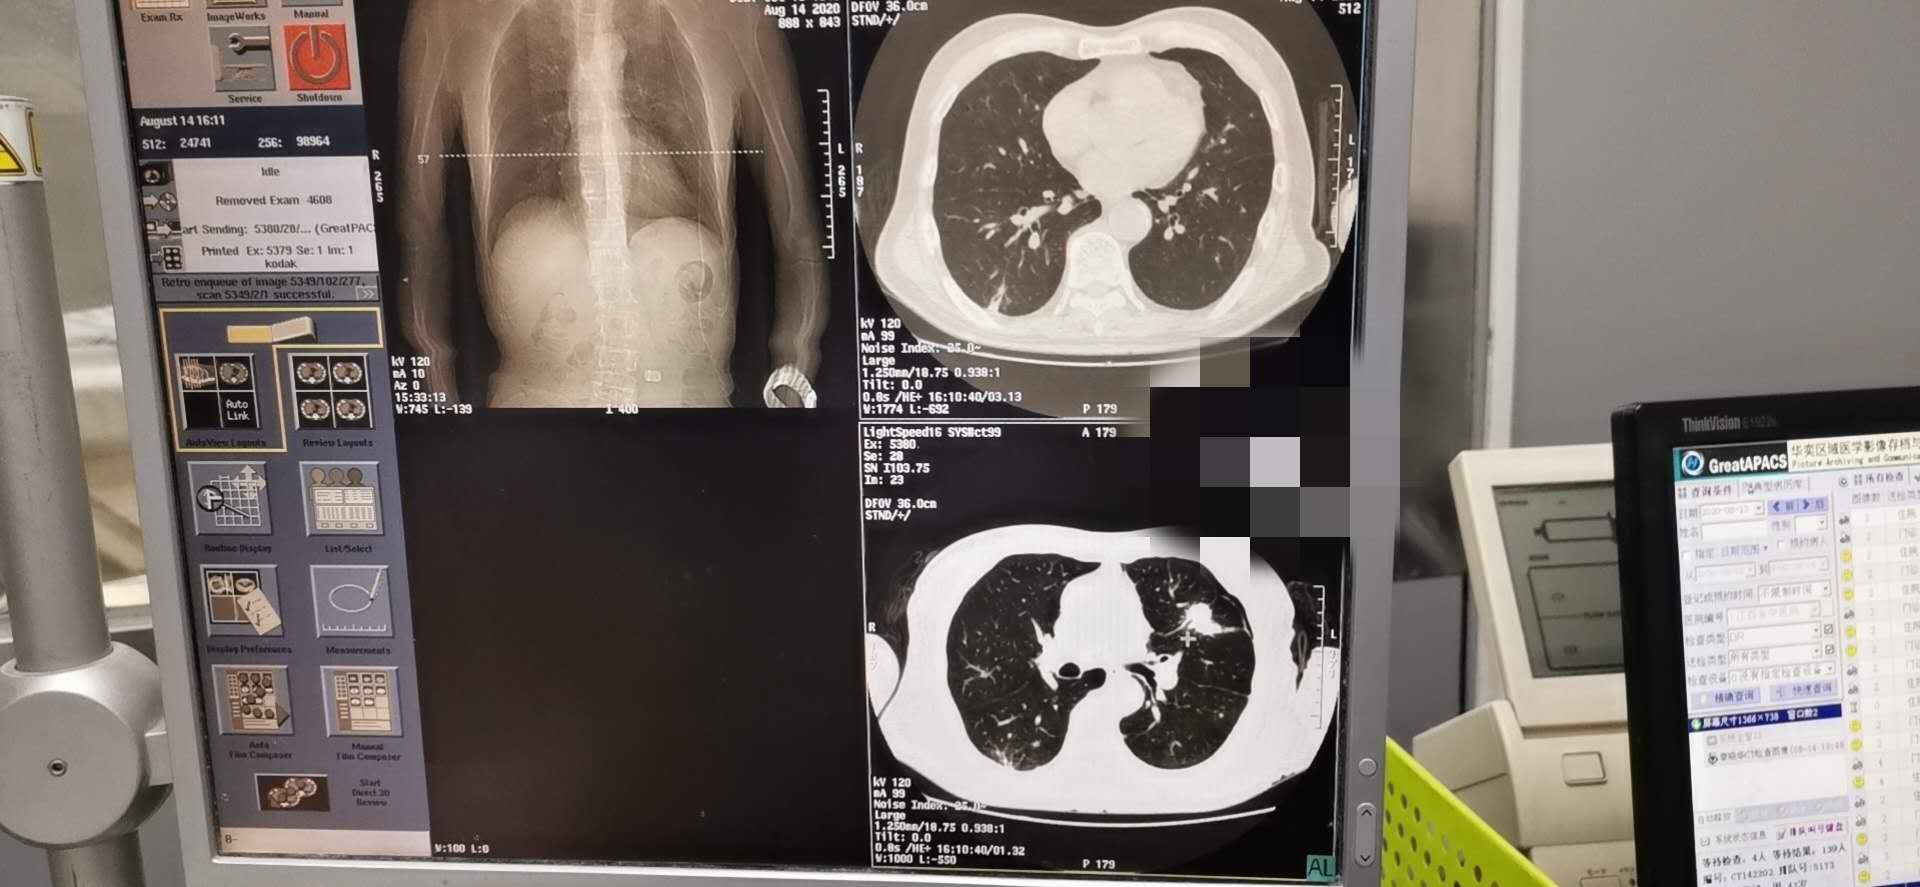

我院肿瘤科8.14于CT引导下完成肺穿刺术

肺癌的发病率及死亡率高居恶性肿瘤之首,早诊断及早治疗尤为关键。 CT引导经皮穿刺肺活检诊断肺部疾患CT引导下穿刺适用范围广,临床应用最多。CT横断层扫描有良好的空间分辨率和密度分辨率,可准确显示病灶的大小、位置及内部情况,以及与血管等周围结构的解剖关系,尤其适用于定位难度大、病灶在肺门及纵隔附近者。当肿块与肺不张、阻塞性肺炎混合后,有时需行增强扫描才能确定肿块的实际大小。方法是指先作CT扫描确定病灶最佳的穿刺点,进针深度和角度,而后进行穿刺活检。常规CT下不能直接观察进针状况,必须在确定进针点后估算进针深度及进针方向,进针后再次扫描确认后方可行穿刺活检。CT引导下穿刺精确度高,对于0.5~1cm的病灶也可在CT导引下成功活检。因此对常规方法未能确诊的肺部结节病变、空洞病变、双肺弥漫性病变及纵隔肺门占位病变,应用CT引导下肺穿刺抽吸和切割针活检能取得较满意结果。尤其直径≤2cm肺部结节活检的准确性较高而并发症较低,可作为肺内孤立性小结节灶定性诊断的首选方法,其操作简单、安全、可靠。

为明确诊断及指导下一步治疗方案。我科洪禹霖副主任医师、张峰浩医师、吁佳副主任护师精诚配合下于8.14日成功完成一例肺小结节穿刺术,术后无明显气胸及出血并发症、患者安返病房。